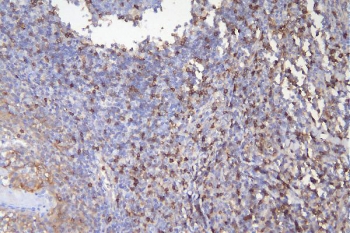

CD5 Antibody for IHC. Immunohistochemistry analysis of CD5 antibody staining in FFPE human tonsil tissue using a T cell lineage marker antibody. Strong membranous staining is observed in interfollicular T lymphocytes with dense labeling of T cell zones surrounding germinal centers, while follicular B cell regions remain largely negative. The staining pattern highlights normal tonsillar architecture and supports the use of CD5 as a defining marker of T cell lineage within lymphoid tissue. Heat-induced epitope retrieval was performed in pH 6 citrate buffer for 20 minutes followed by cooling prior to antibody incubation.